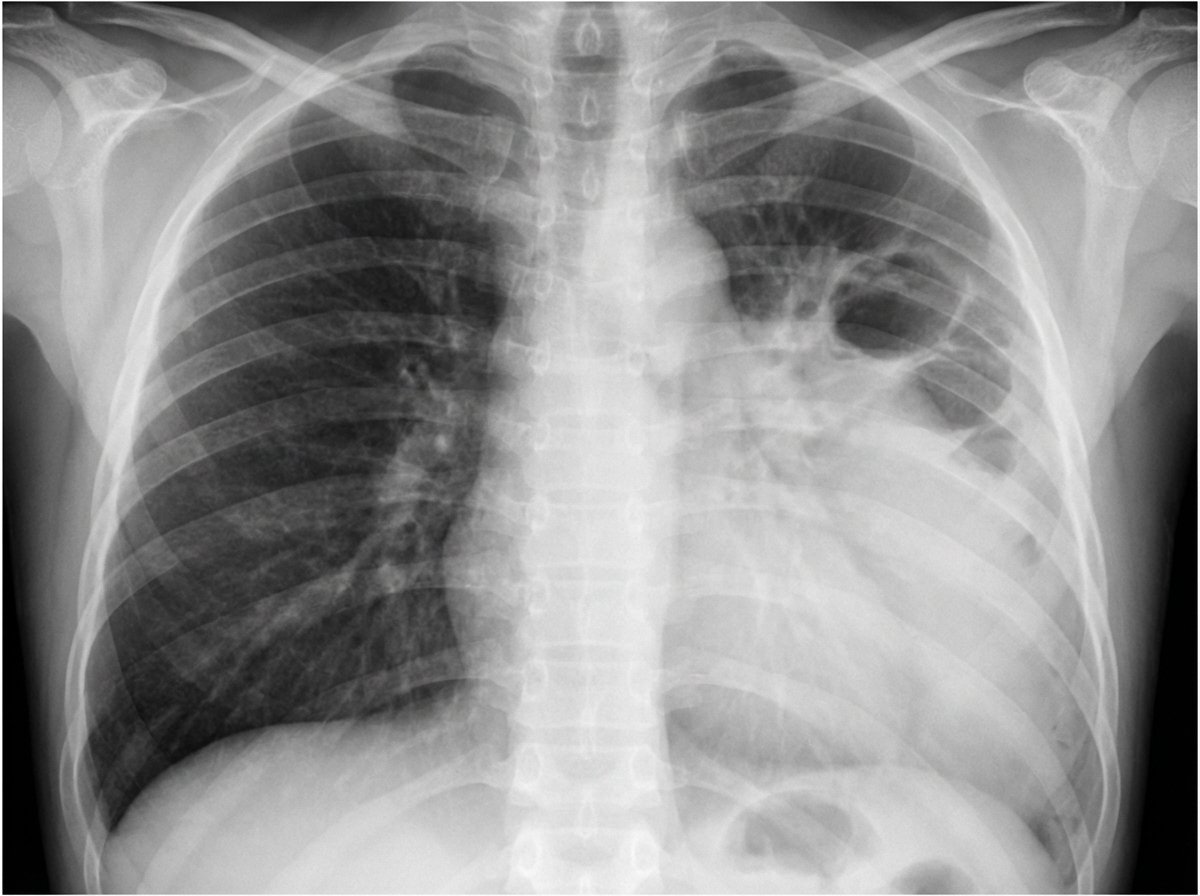

What is the most likely etiology in a 10-month-old child with a 7-day history of high-grade fever, exhibiting the following X-ray findings, and not responding to ceftriaxone?

Explanation: ***Staphylococcus aureus*** - Characteristic X-ray findings in infants include **pneumatoceles**, **empyema**, and **pyopneumothorax**, which are pathognomonic for staphylococcal pneumonia. - Failure to respond to **ceftriaxone** suggests **MRSA**, as ceftriaxone does not provide adequate coverage against methicillin-resistant strains. *Streptococcus pneumoniae* - Typically responds well to **ceftriaxone** therapy, making this unlikely given the treatment failure described. - Usually presents with **lobar consolidation** on chest X-ray without the characteristic cavitary lesions or pneumatoceles seen with staph infections. *Mycoplasma* - Predominantly affects **school-age children** and adolescents, not typically seen in 10-month-old infants. - Presents with **atypical pneumonia** symptoms including gradual onset, dry cough, and bilateral interstitial infiltrates rather than high-grade fever and cavitary lesions. *Respiratory Syncytial Virus* - Causes **bronchiolitis** with hyperinflation and peribronchial thickening on chest X-ray, not lobar pneumonia with cavitary changes. - Typically presents with **wheezing**, **rhinorrhea**, and **cough** rather than high-grade fever and pneumonic consolidation.